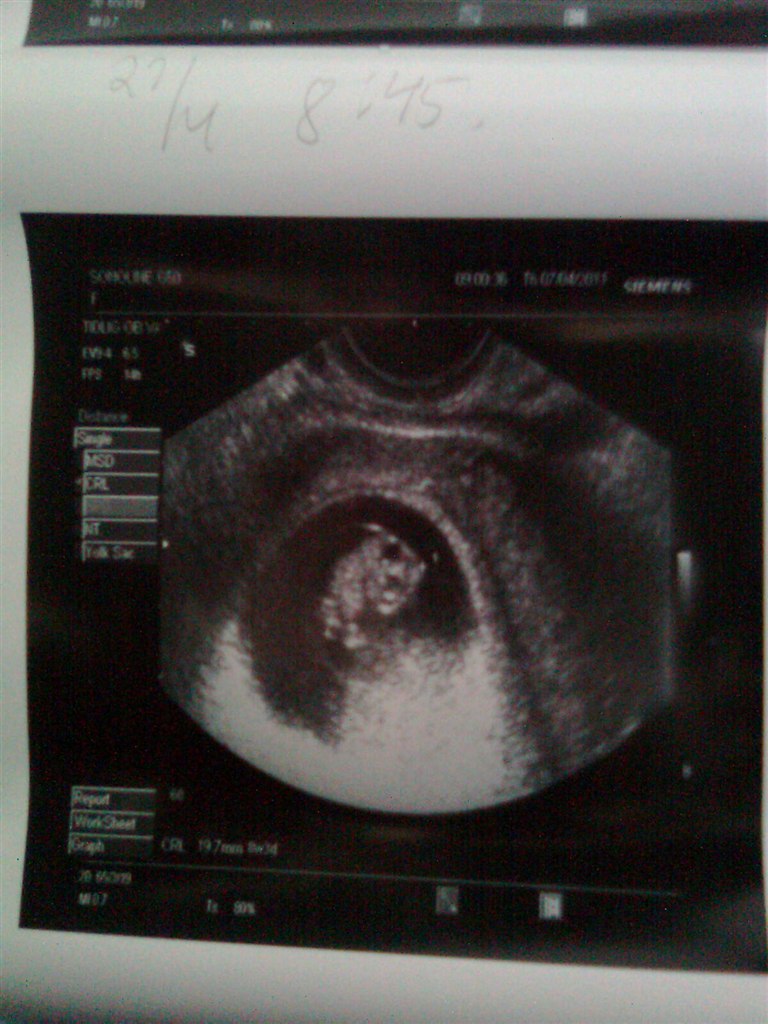

Vores baby har det godt. Hjertet slår derud af  FANTASTISK og se den lille igen  Bebsen har allerede sin moars sove hjerte, den ville simpelhen ikk være med til og hoppe lidt rundt, næh nej, den lå bare helt stille. Men det vigtigste er bare hjertet slår og den er voksede  Har fået hun nu skanning tid d.27.4, da min gynækolog godt kunne tænke sig og se den vinke  også lige inden NF som er d. 4.5

Mia 8+5

Vedhæftede fotos (klik for at se i fuld størrelse)